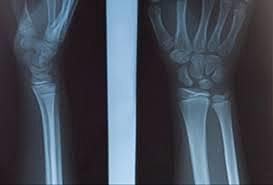

Abraham Colles (1773-1843) nació en Kilkennny, Irlanda. Siendo de origen muy humilde llegó a profesor de cirugía en el Colegio de Cirujanos de Dublín a los 29 años. Fue el primero en ligar la arteria subclavia, pero es más conocido por su descripción de la «fractura de Colles»

John Rhea Barton (1794-1871) describió la «fractura de Barton» de la muñeca.

Sir Robert Jones (1855-1933). Realmente para muchos es el cirujano ortopédico más grande que el mundo ha conocido. Jones publicó el primer artículo del uso clínico de los rayos X para localizar una bala en una muñeca.